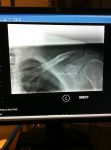

Out for a nice afternoon training ride today when disaster hits....Windy+reaching for water bottle equals crash.

Finished another 5km or so and went home.  After visiting the hospital it is a broken collar bone.  Timing sucks, but I am hoping I can be in good enough condition to still ride in June.

Such a bummer........helmet saved me for sure.  Ill find out Thursday if i need surgery.  What are my chances of being ready for June 8?

No surgery will be required and after weekly Xrays and doctors appointments, the doctor is confident that I am healing at a good pace.

Six weeks ago today since my accident.

First time back in the saddle and managed to tough out 34 km.  I am hoping for doctor clearance at my appointment on Thursday.  It well no doubt be a challenge to ride 227km with no little training put in, and obviously the still tender shoulder, but if its one thing i have is determination!